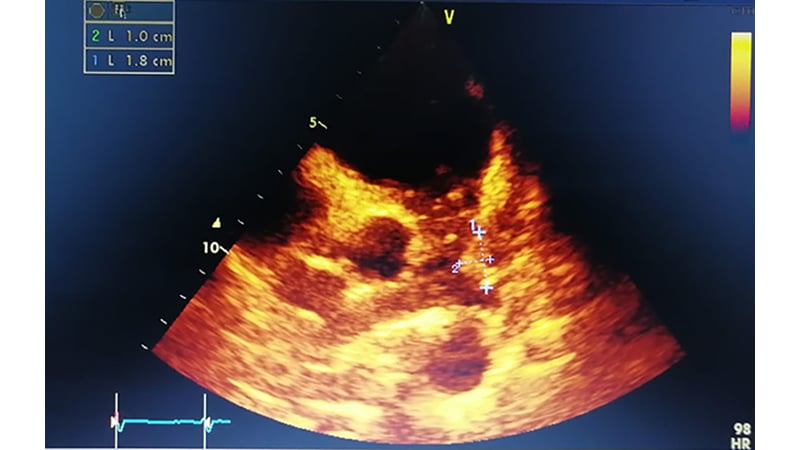

Endocarditis Sobre Valvula Aortica Nativa Causada Por Staph Aureus Caso 81 Infectosos El Blog De Las Enfermedades Infecciosas. Las manchas de roth son hemorragias retinales (retinianas) con centro pálido o de color blanco compuestas y rodeadas de fibrina coagulada o cúmulos de hematíes. Las manchas de roth son hemorragias retinales (retinianas) con centro pálido o de color blanco compuestas y rodeadas de fibrina coagulada o cúmulos de hematíes. El término endocarditis suele referirse a la infección del endocardio (es decir, una endocarditis infecciosa). Other structures that may be involved include the interventricular septum, the chordae tendineae, the mural endocardium, or the surfaces of intracardiac devices. Endocarditis infecciosa (mancha de roth). Inicio medicina clínica manchas de roth y endocarditis infecciosa. Las manchas de roth son uno de los tipos de enfermedades vasculares, que constituye una de las primeras causas de muerte en todo el mundo. Estas manchas pueden observarse en el fondo de ojo mediante el uso de un oftalmoscopio. Las manchas de roth generalmente son causadas vasculitis mediada por inmunocomplejos debido a la endocarditis bacteriana, también pueden ser observadas en se han atribuido a embolias sépticas en la piel. También puede incluir la endocarditis no infecciosa, que consiste en la formación de trombos estériles compuestos de plaquetas y fibrina en. Estas manchas pueden observarse en el fondo de ojo mediante el uso de un oftalmoscopio. The roth spot o la mancha de roth deriva de moritz roth, un patólogo suizo que describió manchas blancas retinianas y manchas rojas un punto o mancha de roth, visto más comúnmente en la endocarditis bacteriana aguda, es un punto rojo (causado por hemorragia) con un centro. Endocarditis is an inflammation of the inner layer of the heart, the endocardium. It usually involves the heart valves. En realidad, las de roth se encuentran entre las enfermedades o síntomas que son causas de la endocarditis infecciosa.